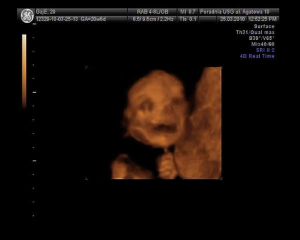

nie wiem czy jeszcze komu¶ się chce to czytać. blog przestał być już biegowy, więc chyba stracił rację bytu. ale napiszę, co mi tam :) i nawet wstawię zdjęcie potomstwa, które siedzi w moim brzuchu. w zeszłym tygodniu okazało się, że to dziewczynek. a przynajmniej na 95%, bo nie bardzo chciało się odwracać i pokazywać co tam ma :)